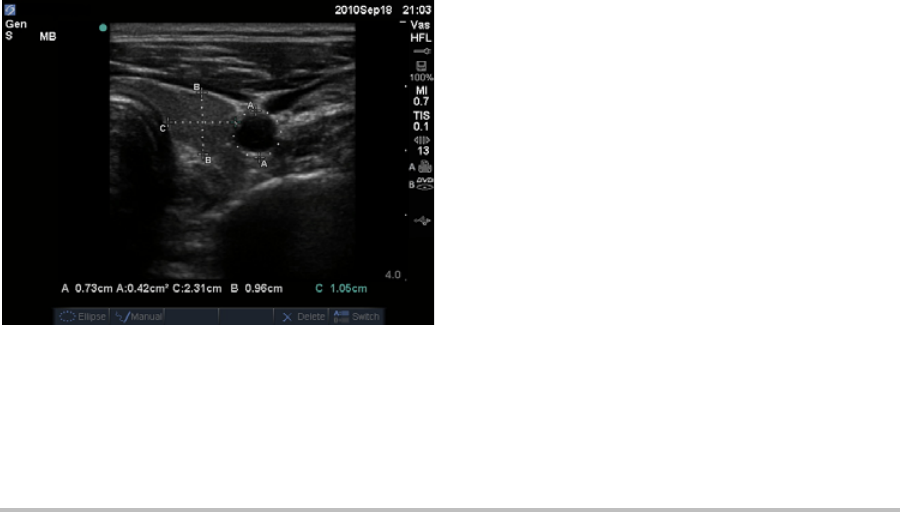

Percent reduction calculations ......................................................................46

Volume calculations ..........................................................................................48